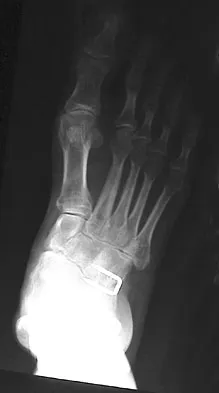

Figure 1 shows the radiograph of an 11-year-old boy who stubbed his great toe while playing soccer barefoot. He is able to walk home despite a small amount of bleeding at the nail fold. Management should consist of

Great toe fractures through the physis should be considered open fractures if there is bleeding at the nail fold. Treatment should include irrigation and debridement and appropriate antibiotics. Immobilization with a cast is usually sufficient for treatment of the fracture. Noonan KJ, Saltzman CL, Dietz FR: Open physeal fractures of the distal phalanx of the great toe: A case report. J Bone Joint Surg Am 1994;76:122-125.